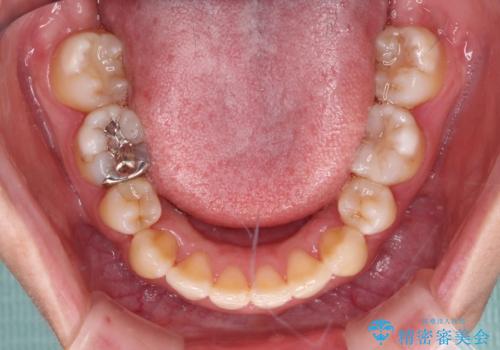

- 上下前歯のデコボコを気にして来院された患者様です。

デコボコが強いため、非抜歯で矯正をすると出っ歯仕上がりとなるため、上下左右の第一小臼歯4本を抜歯することとしました。

当初予定は2年半程度と伝えていましたが、2年にも満たない期間で治療を終えることができました。